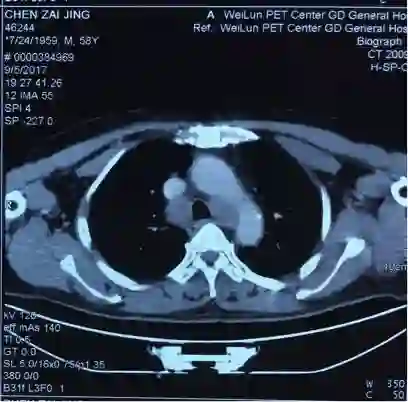

5. 2017-9-5广东省人民医院PET提示:右肺下叶肿物2.8*2.7cm,SUV 22.3,双侧颈部、双侧气管旁、隆突下、食管旁、右侧肺门淋巴结肿大,代谢升高,考虑为转移灶,右侧肾上腺转移灶,具体结果见下图:

7.目前诊断:右下肺肿瘤cT1cN3M1c IVB期(颈部淋巴结、肾上腺)

2.  根据PET/CT目前诊断为右下肺肿瘤cT1cN3M1c IVB期(颈部淋巴结、肾上腺)

吴一龙医生这个病例的PET-CT有一个特点,右肺下叶的病灶并不大,2.7*2.8cm,但是代谢非常高,高达22.3。这种小病灶高代谢的病灶,在肺癌患者中比较少见。尤其是代谢值大于20但病灶小的情况很少见。我同意谢主任刚的意见,如果该患者没有肾上腺的病灶,我认为诊断可以到此为止。我们可以看到,肺内的病灶有可能是肺内的淋巴结,我们已经对最大的淋巴结进行了活检,为良性病灶。但是,由于该患者多了肾上腺的病灶,用刚才的说法无法解释,肾上腺不属于淋巴系统。结合既往我们遇到的病例,我们现在有两个办法,我认为对于该患者,观察是一个办法,但是如果漏诊会比较麻烦,如果观察一段时间,下次过来复查提示病灶稍增大,我们如何处理?因此我认为现在我们要明确诊断,需要取病理活检,但是是取肺部病灶还是肾上腺的病灶?